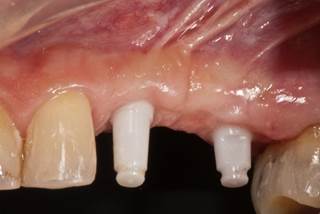

Hasta hace poco tiempo solo existían implantes de cerámica de una sola pieza por razones técnicas. Para el implantólogo es más difícil y requiere más práctica colocar este tipo de implantes en su posición óptima. El diagnóstico en 3D es una ayuda importante para lograrlo. En los primeros 2 meses, mientras se produce la osteointegración del implante, el profesional tiene que buscar para cada caso la mejor forma para proteger el pilar del implante que sobresale de la encía contra fuerzas que puedan provocar micro movimientos del implante que harían fracasar la correcta integración, es decir, la pérdida del implante. Además, el paciente tiene que tener especial cuidado, como por ejemplo no masticar en el lado del implante insertado. Con el avance tecnológico, ya es posible contar con implantes de circonio de dos piezas parecidos a los implantes de titanio. Parece que los resultados clínicos son favorables y nos permite simplificar el protocolo.